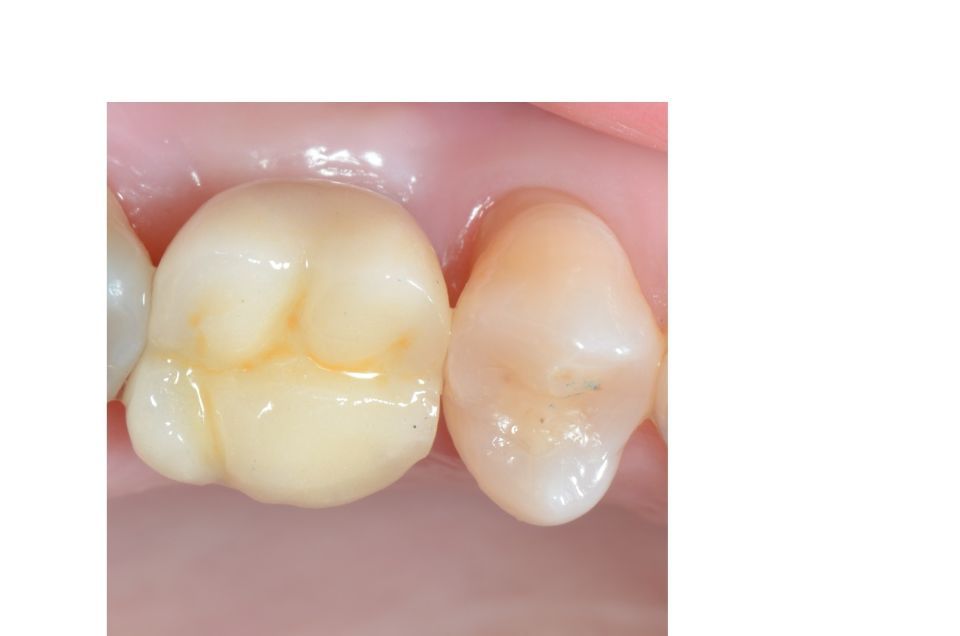

Prosthetic rehabilitation

Oral rehabilitation is the part of dentistry that is concerned with restoring oral aesthetics and harmony through dental prostheses, always looking for a correct occlusion and function. It integrally combines the areas of fixed prosthesis, removable prosthesis, operative, occlusion and dental implant.

When carrying out the treatment plan, appropriate to the patient, an attempt will be made to recover their oral health through the most modern rehabilitation techniques; establishing a close relationship with the other disciplines of dentistry, such as periodontics, endodontics and orthodontics. To achieve the best result.

By means of current dental techniques, it is possible to carry out these restorations by means of fixed prostheses on teeth or dental implants in more than 95% of patients, thus avoiding the use of removable prostheses that are always uncomfortable and in many cases impossible to bear.